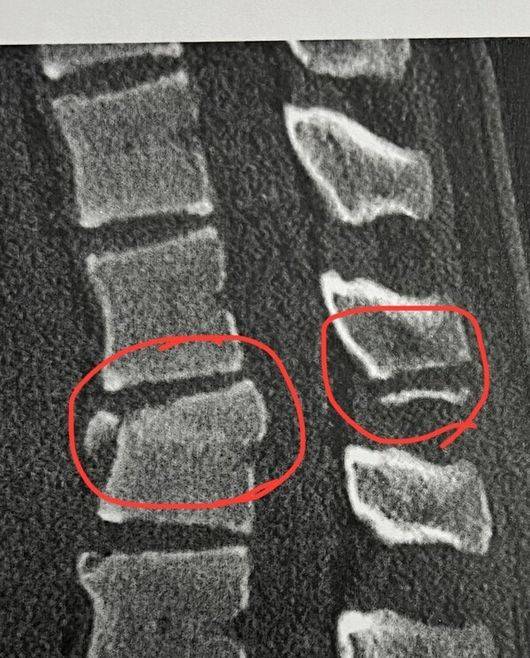

이어 "불과 2년 전, 15살 때 락스에서 스노보드 인생을 끝낼 수도 있었던 큰 부상을 겪었다. 현지에서 척추 압박골절로 긴급 유합 수술을 받았고, 다시는 스노보드를 할 수 없을 것이라는 이야기를 들었다"라며 "열흘 뒤 세균 감염으로 긴급 입원하게 됐다. 염증 제거를 위한 2차 수술과 척추뼈에 골반뼈를 이식하는 3차 수술까지 이어졌다"고 설명했다.